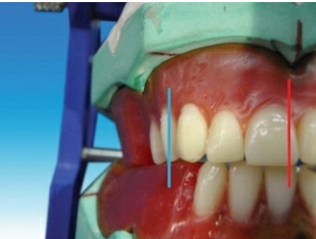

Steps in placement of maxillary second molar

The long axis of the maxillary second molar (blue line) is distally

inclined in relation to the vertical axis (red line) when viewed from the front .

All the cusps are short of the occlusal plane (black line).

The maxillary second molar is slightly buccally inclined when viewed from the front. The buccal surface of the maxillary second molar is barely visible when viewed from the front